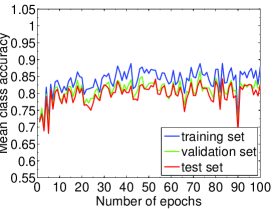

We highlight that training-relevant hyper-parameters can significantly affect the convergence of cost function, the learning speed and the generalization capability of the network. Their impacts are demonstrated via the learning curves of MCA on training, validation and test sets shown from Fig. 4 to Fig. 8. In each figure, we focus on one hyper-parameter while the others are set to their optimal values in Table 2.

Fig. 4 LABEL:sub@subfig:lr1 indicates that when learning rate is small, e.g., , the learning process is so slow that the MCA of the three sets have not become stable in epochs. Properly increasing the learning rate effectively improves learning efficiency and the MCA becomes stable in epochs, as shown in Fig. 4 LABEL:sub@subfig:lr2. At the same time, an over-large learning rate, e.g., , will destabilize the learning process and degrade the classification performance. Also, Fig. 5, 6 and 7 demonstrate the impacts of mini-batch size, momentum and weight decay, respectively.

The comparison in Fig. 8 shows that the dropout strategy (Hinton et al., 2012) shall be used cautiously. When dropout with ratio of (randomly setting the activations to zero with probability of ) is applied to the first fully-connected layer of our CNN system, the learning process becomes slow and fluctuated on ICPR2014 cell dataset. A stabler and faster learning process without overfitting on the test set is gained when removing dropout, as well as better classification performance. This indicates that the neurons at the first fully-connected layer may have to work together to distinguish different staining patterns. In light of this, we decide not to employ dropout when training our network on ICPR2014 dataset.